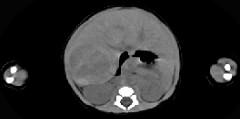

男,5天,上腹部膨隆,CT所见如图,最可能的诊断是()A.原发性肝癌B.肝母细胞瘤C.肝血管瘤D.肝脓肿E.肝转移瘤

问题 男,5天,上腹部膨隆,CT所见如图,最可能的诊断是()

选项 A.原发性肝癌 B.肝母细胞瘤 C.肝血管瘤 D.肝脓肿 E.肝转移瘤

答案 B